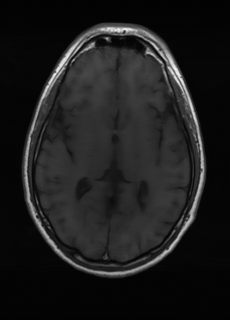

As we observe from the right image in Fig. 2, our BRM, both from MIMO and SISO settings, predicts the performance of dedicated models with a high correlation. We further choose the best three , and perform the last stage of fine-tuning accordingly to (6). A visual evaluation on real data is shown in Fig. 3. For simulated data, please refer to the Supplemental Material section.

Base on the best performing , we perceive that among , , and FLAIR, the results are best when is sampled the most. We suggest that this makes intuitive sense as images provide the best contrast out of the three sequences, which can compensate for the details lost in other images. The same observation can be made on the simulated data, where both and FLAIR show good contrast. When the time setting is changed to non-uniformity, we can see that our search for the best sampling strategy reflects the change. is sampled more as a result of faster acquisition time, while is still sufficiently sampled.